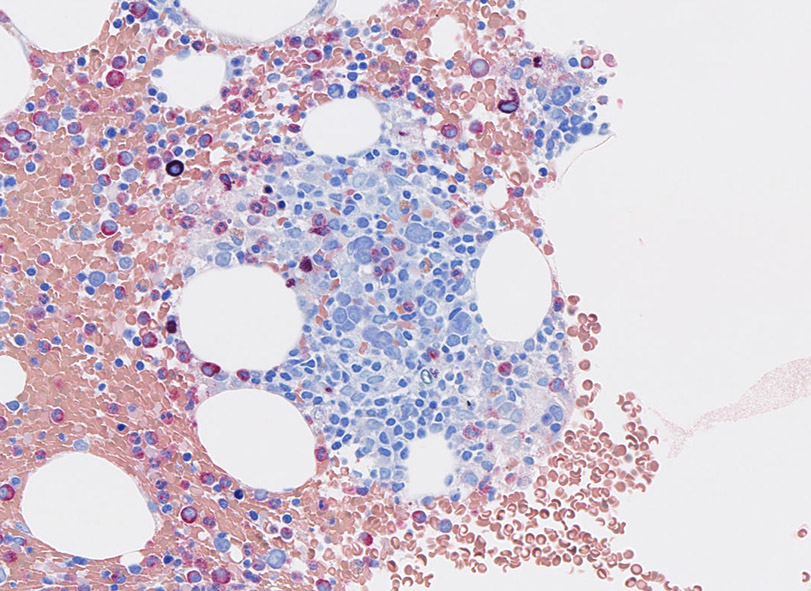

Bone marrow組織所見(clot section);

免疫染色

CD3とCD20

CD4, CD8とcytotoxic granulesの免疫染色

CD4陽性細胞の多くはマクロファージ. CD8+, toxic molecule+ のT-cellが増加している.本例では, TIA1陽性細胞が増加しているが, granzymeB陽性細胞はそれほど多くない.